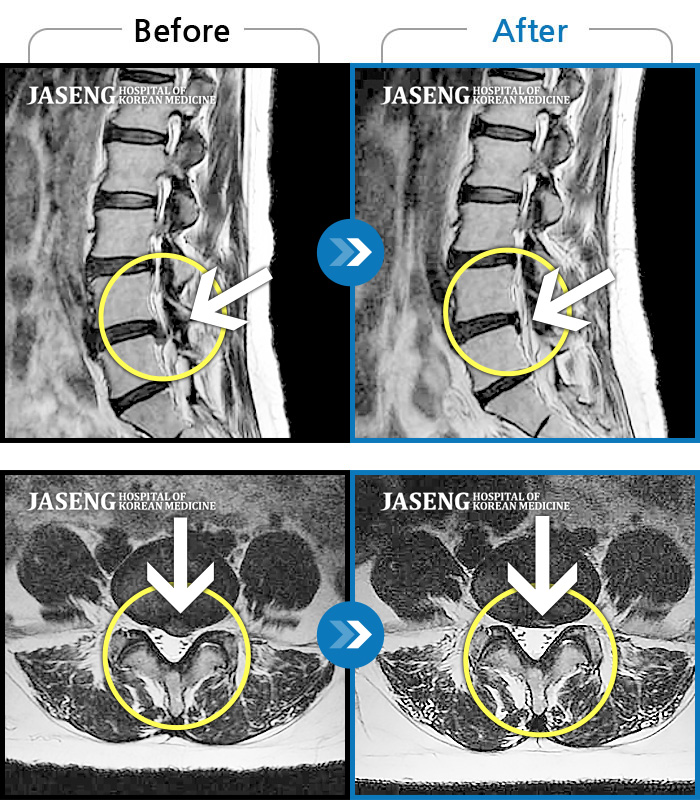

허리디스크

수원 · 김태성 원장

허리 통증과 좌측 대퇴부 저림과 당김

촬영시기

2023.02.03 ~ 2024.02.14

2024.11.21